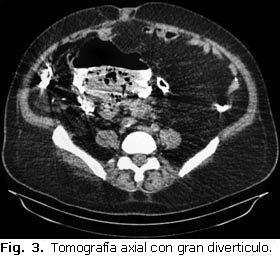

Posteriormente se realiza una tomografía axial simple del abdomen y se concluye como un divertículo gigante de colon sigmoides perforado (Fig. 3).